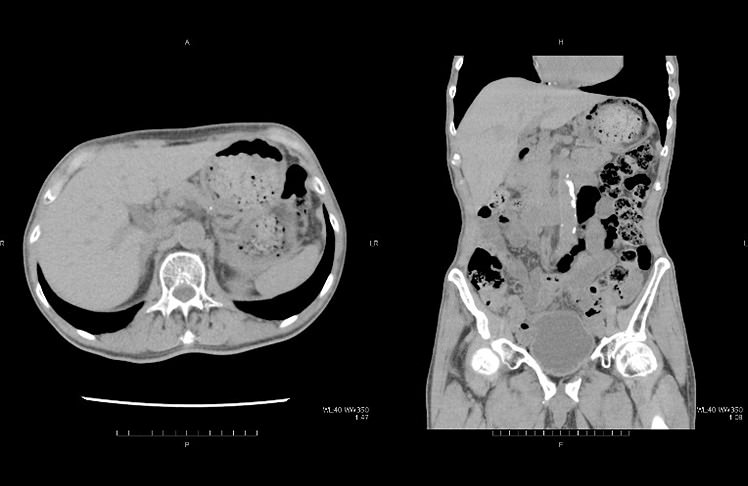

全身ドック

全身ドックは、頭部MRI・MRAによる頭蓋内精査、胸部〜骨盤部CTによる肺や腹部実質臓器の精査、冠動脈の石灰化スコア算出による虚血性心疾患リスク解析および骨盤部MRIによる、男性は前立腺、女性は子宮・卵巣の精査を行います。CTやMRIによる全身のスクリーニングを行うことができます。